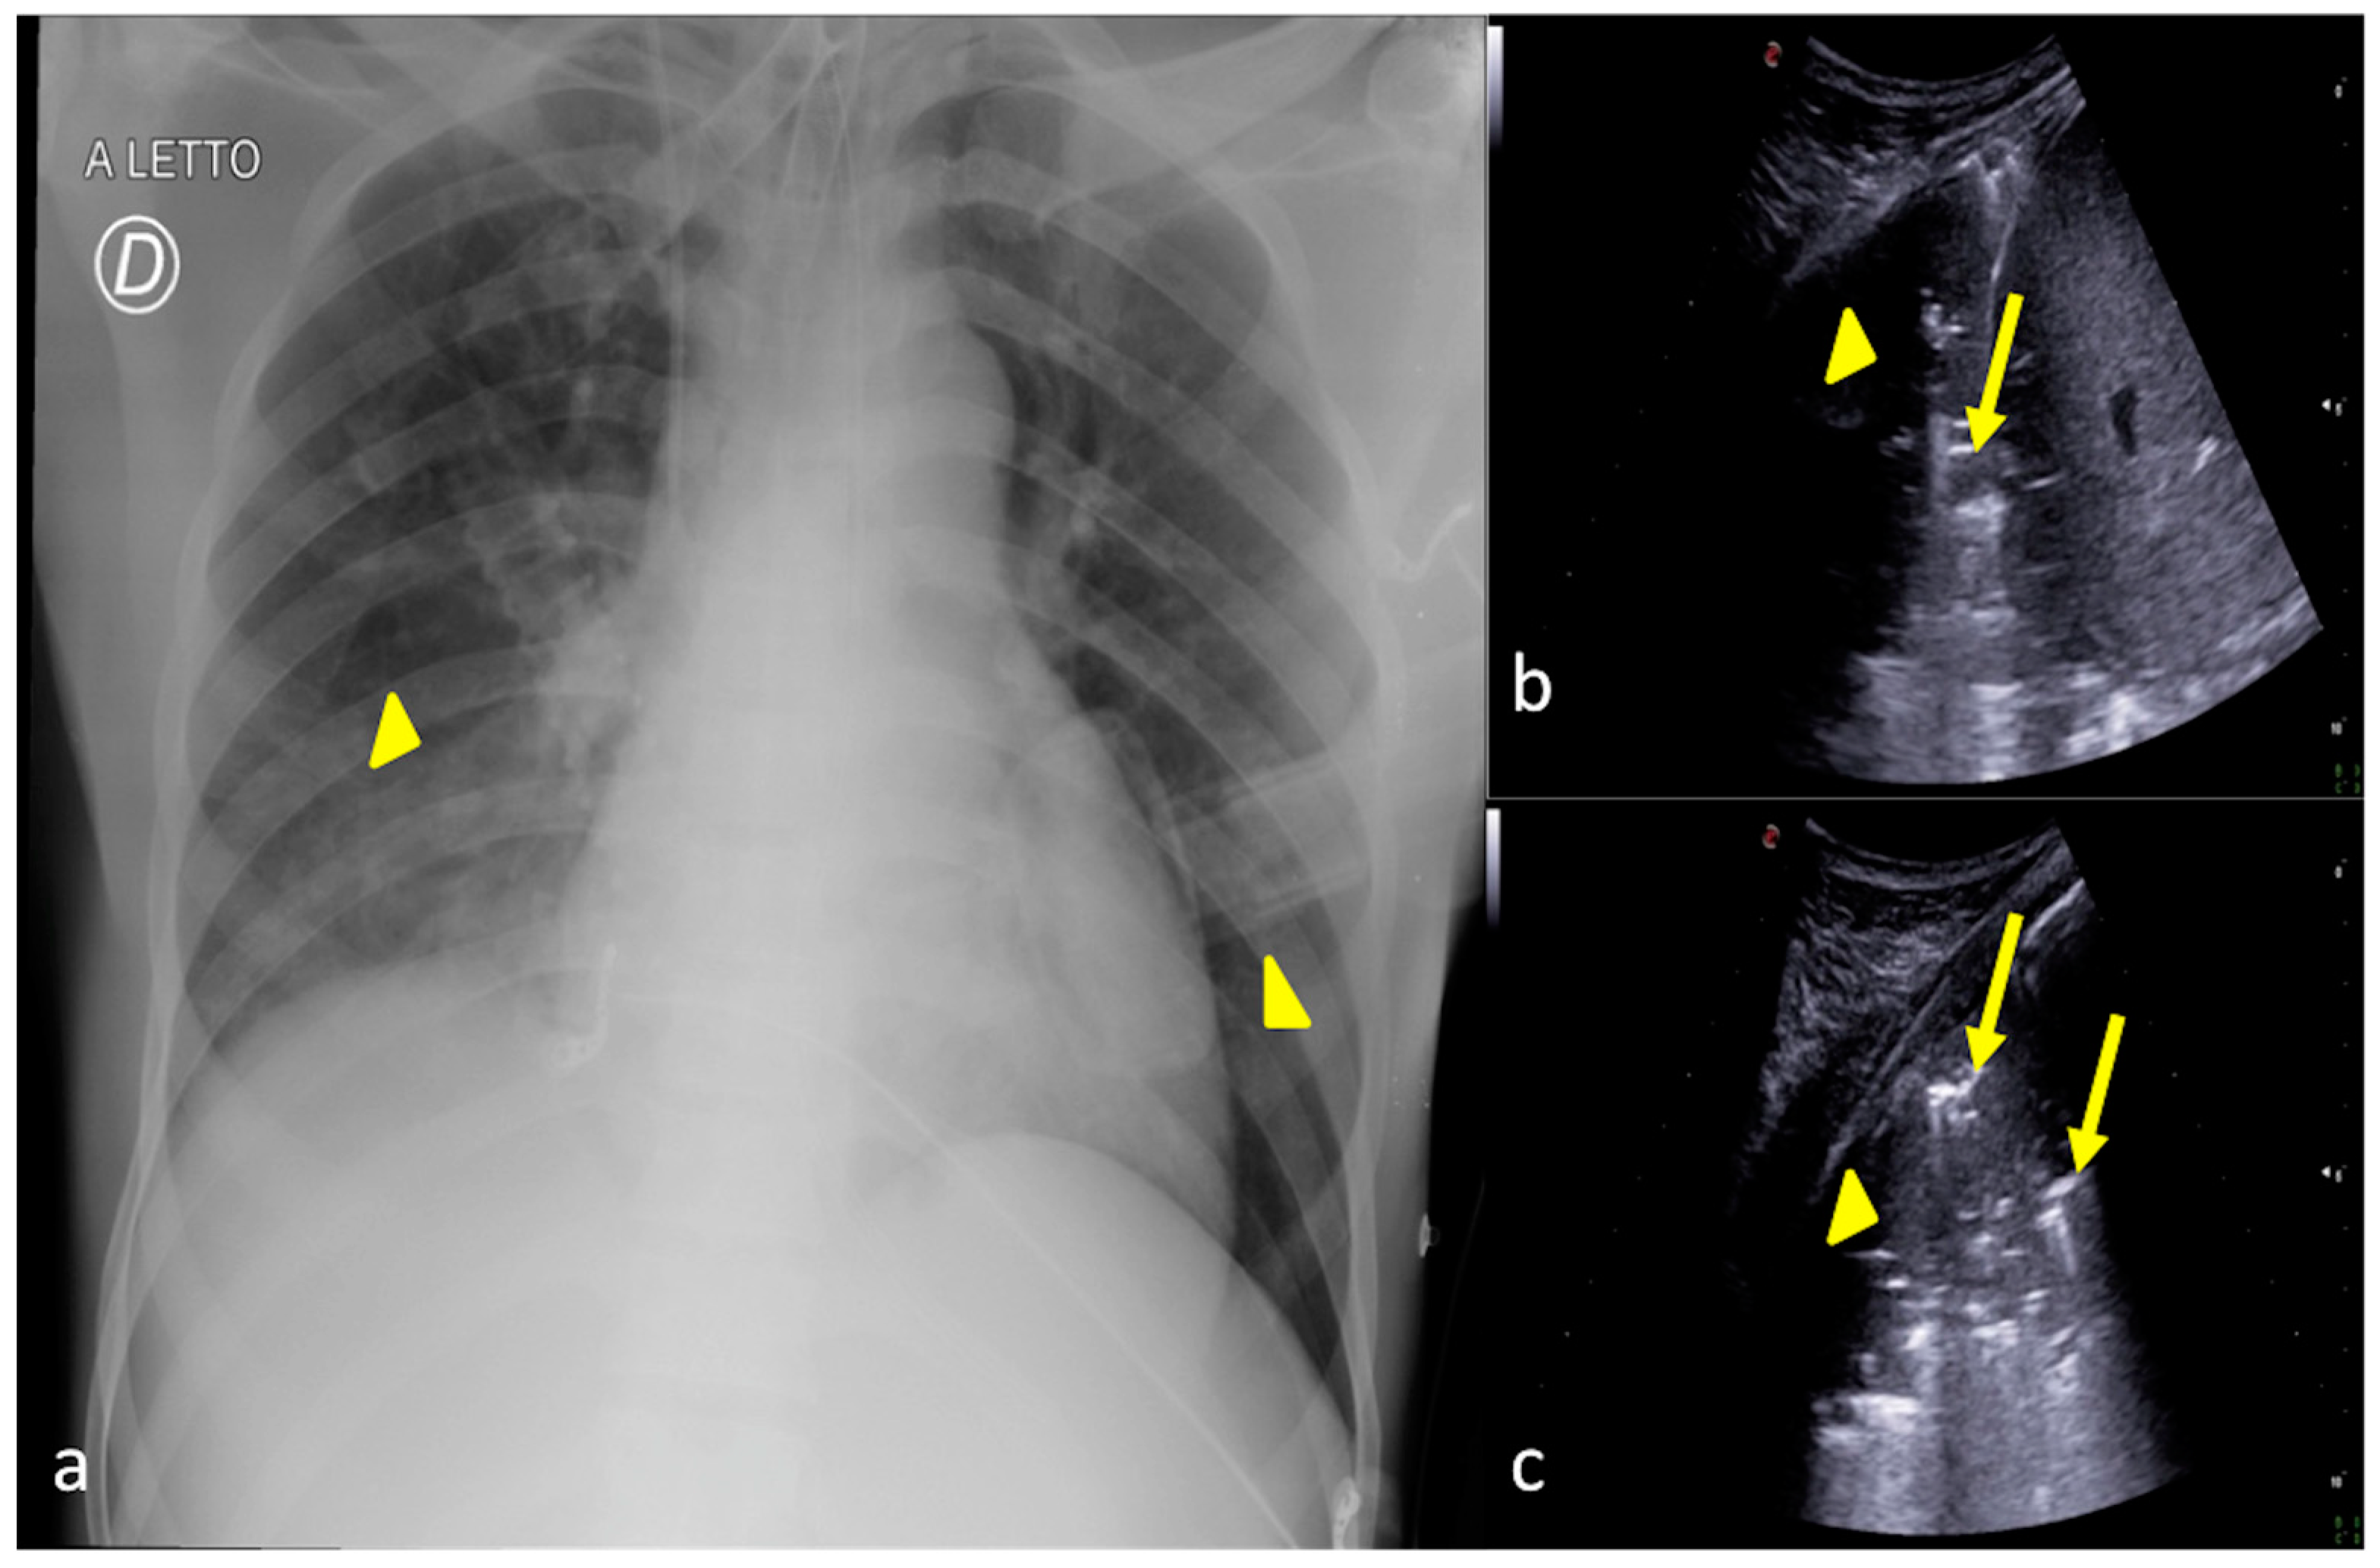

2.2. Pneumonia

2.3. Pleural Effusion